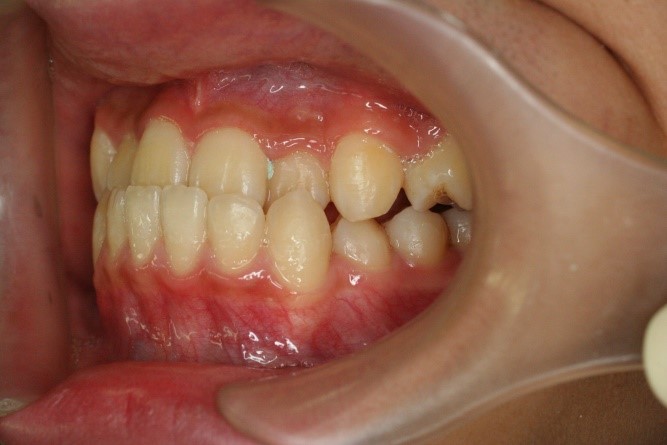

症例02|20代の男子

前歯部の反対咬合の症例

上下の前歯が反対咬合を主訴として来院されました。通常通り検査を行い「反対咬合」と診断されました。

治療計画

下の犬歯から後ろの歯をまずは後方に移動して、その後に上下の歯並びを綺麗に並べて前歯部の咬み合わせを改善することにしました。

矯正の種類

カリエールディスタライザー、上に裏側、下に表側のセラミック(白い矯正装置)

治療前の写真を治療後の写真を比べると、鼻の下がくぼんでいたのが改善されて口元が綺麗になった事が解ります。また歯並びは綺麗に並び上の歯が前に出て下の歯が後ろに移動して歯がしっかりと咬み合っています。

患者様に協力いただけたため、2年の治療期間で終了することができました。